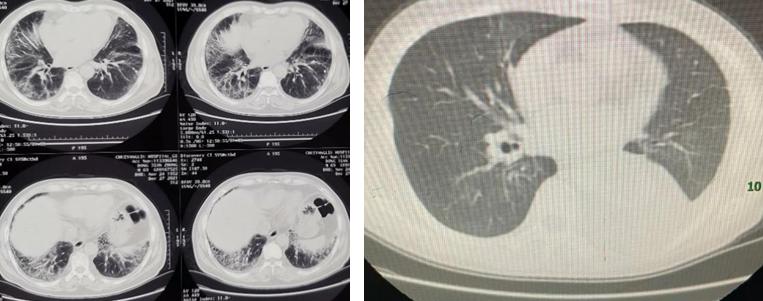

图2: 针对患者出现的间质性肺炎、给予激素治疗前后的胸部CT

2021年7月22日开始服用奥希替尼80mg,每日一次,每28天一周期,大约4周后复查CT,疗效评价为疾病稳定,患者胸闷气短症状也明显改善,此后每8周左右复查一次。患者口服奥希替尼5月,肿瘤继续缩小到1.0 cm*0.5 cm,肿瘤缩小 34%,但在2021年12月患者自觉呼吸困难,做CT复查发现双肺多发斑片、类结节影,考虑药物相关性间质性肺炎可能性大(图2)。向患者及家属交代目前出现胸闷、憋气,可能与患者出现间质性肺炎有关,建议患者停用原来奥希替尼,给予吸氧、激素治疗,然后观察治疗反应,一方面观察患者症状改善情况,另一方面可以通过自测血氧饱和度的数值进行跟踪,再结合后面CT复查结果,来追踪患者肺部情况。

而且向患者家属比较了以下三代EGFR-TKI的三个药物奥希替尼、伏美替尼、阿美替尼的安全谱及药物可及性,发现阿美替尼的皮疹、腹泻、间质性肺病、心*毒脏**性发生率更低;基于保证疗效降低毒副作用的综合考虑,因此将奥希替尼调整为阿美替尼作为该患者的治疗方案:2021年12月20日就给冯女士换用了阿美替尼110mg,每日一次,每28天一周期进行治疗,一月后复查肿瘤稳定,冯女士药物相关间质性肺炎也明显改善、未出现肝功能损害等副作用,定期复查胸部CT,治疗效果理想。